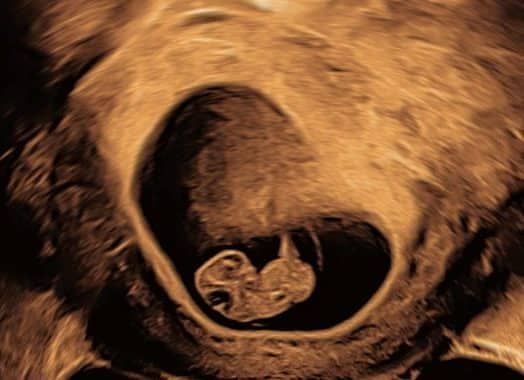

En graviditetsscanning er en ultralydsundersøgelse, hvor man ved hjælp af lydbølger kan se fosteret inde i livmoderen. Scanningen bruges til at bekræfte graviditeten, vurdere fosterets udvikling og tjekke, om alt ser normalt ud.

Tidlig scanning gravid, tænker du måske?

Det giver fint mening at få en tidlig scanning eller en tidlig graviditetsscanning som det også kaldes. Graviditetsscanninger kan give dig tryghed for at graviditeten sidder korrekt i livmoderen og at den udvikler sig som den skal. Herudover kan du få et korrekt estimat for din termin. Vi anbefaler ikke at du følger din graviditet med scanninger uge for uge, men det er ikke noget som skader barnet.

I danmark tilbydes der to scanninger i løbet af graviditeten. Den første er en nakkefoldsscanning i uge 11-14, og den anden er en misdannelsesscanning i uge 18-22. Man kan vælge at tilkøbe flere scanninger selv. Det er ikke dækket af sygesikringen. Hvis der er komplikationer bliver du fulgt tættere på hospitalet uden at skulle betale for det. Se hvilke scanninger vi tilbyder her: Graviditetsscanninger

Hvad kan man se ved graviditetsscanninger?

Ved en graviditetsscanning kan man blandt andet se, hvor langt henne graviditeten er, om der er liv, antallet af fostre og hvordan fosterets organer og vækst udvikler sig. Senere i graviditeten kan man også se barnets køn, hvis man ønsker det.